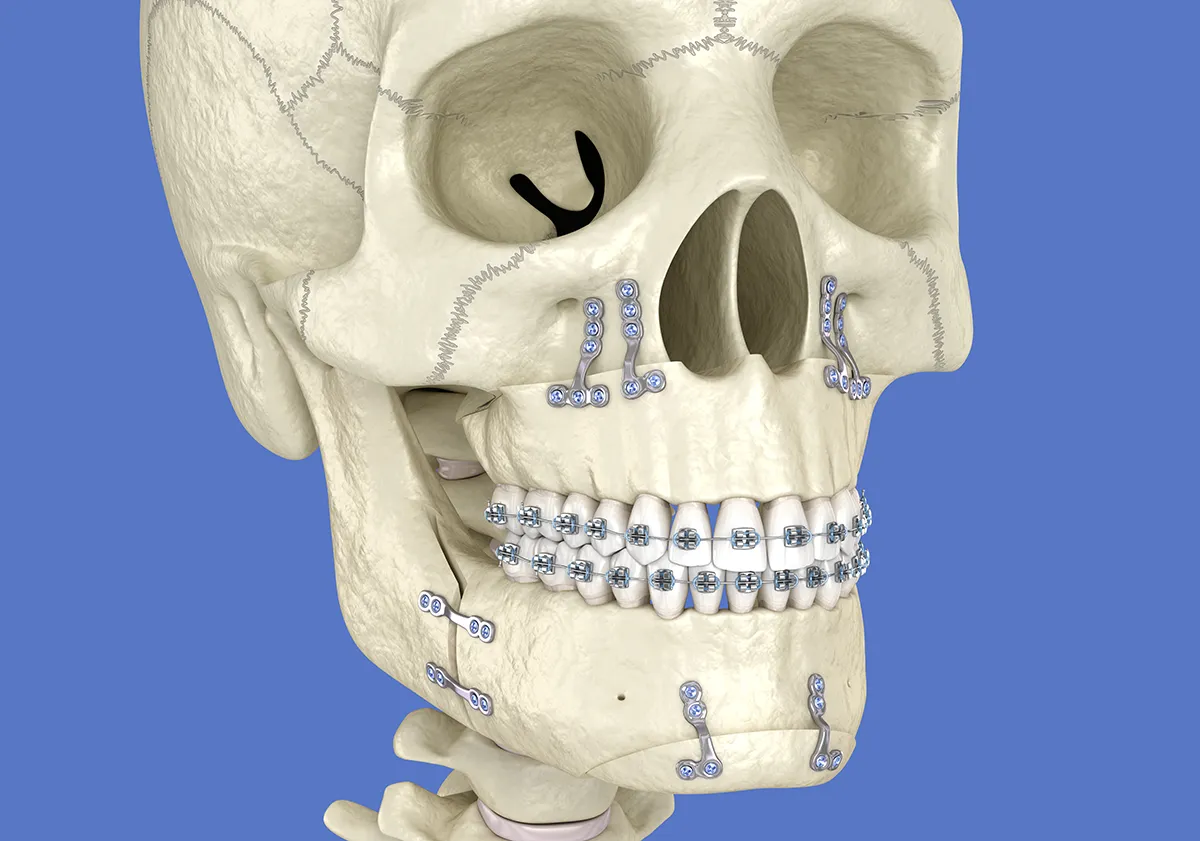

• Le maxillaire et la mandibule sont repositionnés en même temps.

• Fixation avec des mini-plaques et vis en titane.